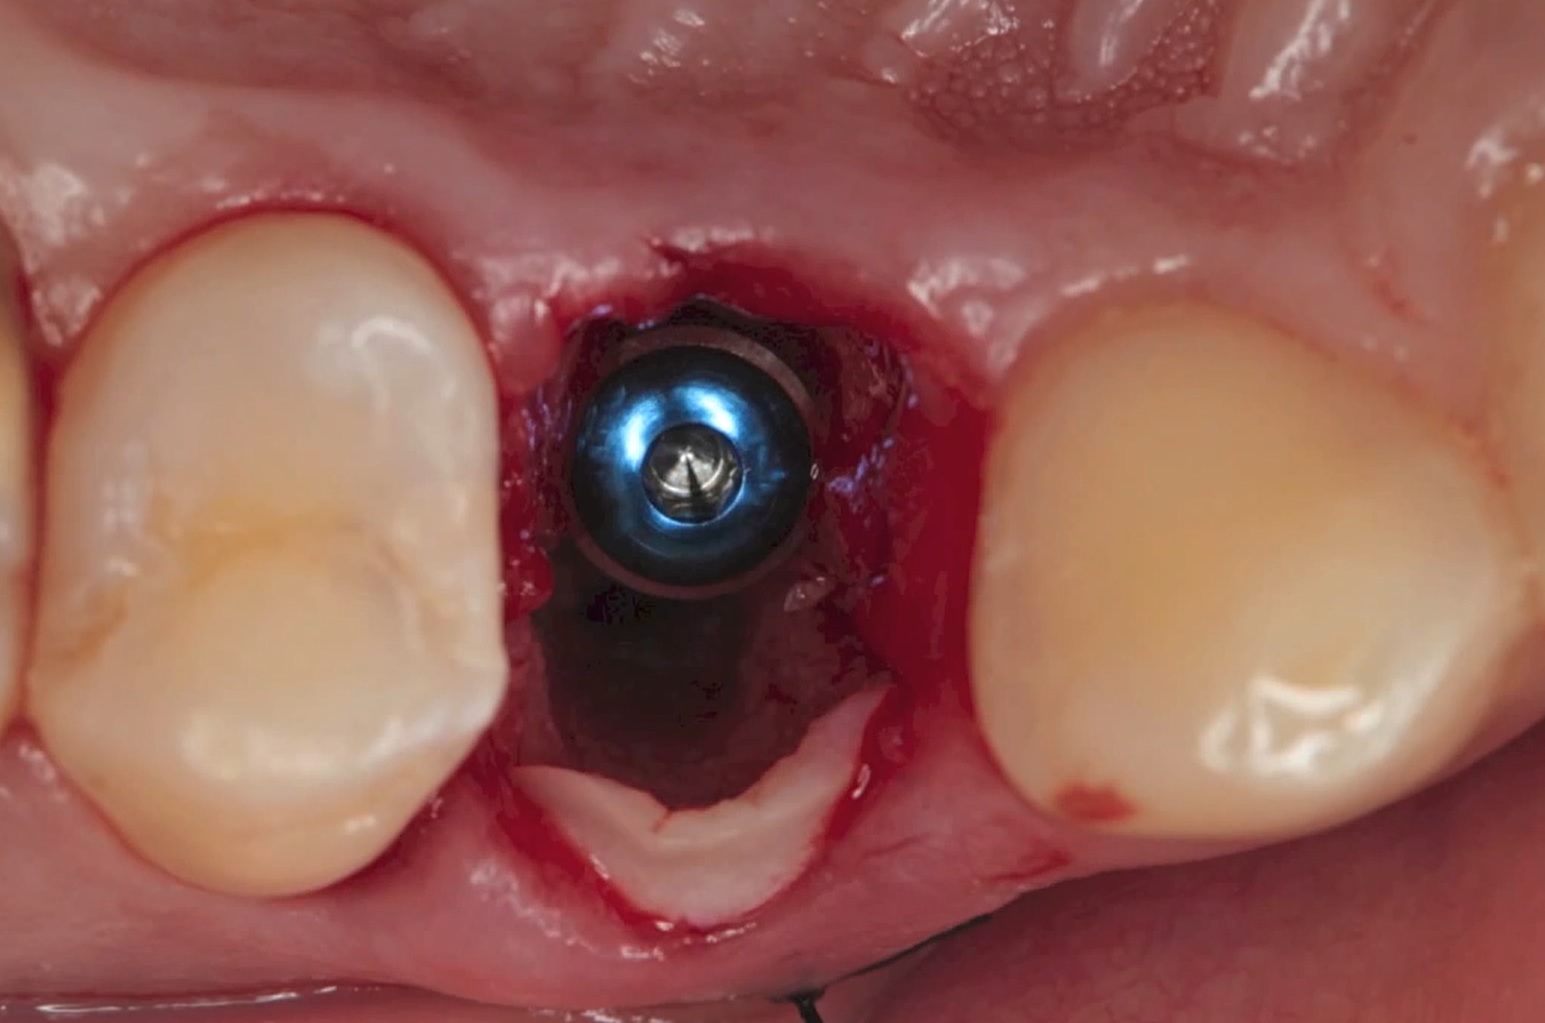

Dr Segin Chandran,Single replacement,Bone regeneration,Digital Guided Surgery,Maxillary Posterior,#25,Immediate Placement,Sinus Elevation,Guided surgery,AnyRidge,R2GATE Guide,R2GATE Surgical Kit(AnyRidge),MICA,Crestal elevation,Minimally invasive,Video